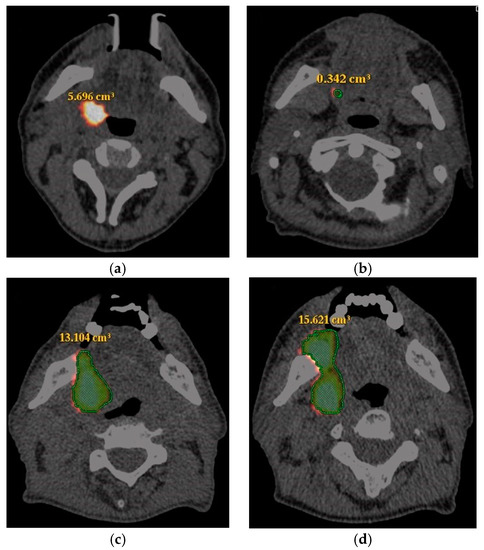

2.4. Image Interpretation